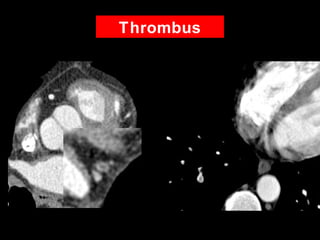

Thrombus

• 42 YOM

• Epigastric chest pain

• Risk Factors

– Hypertension

– Smoker

• No calcium

20 HU

Acute Posterior Wall Infarction